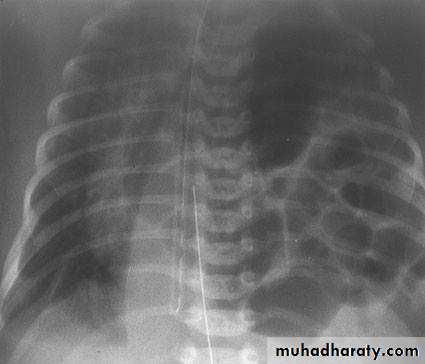

Lung contusion